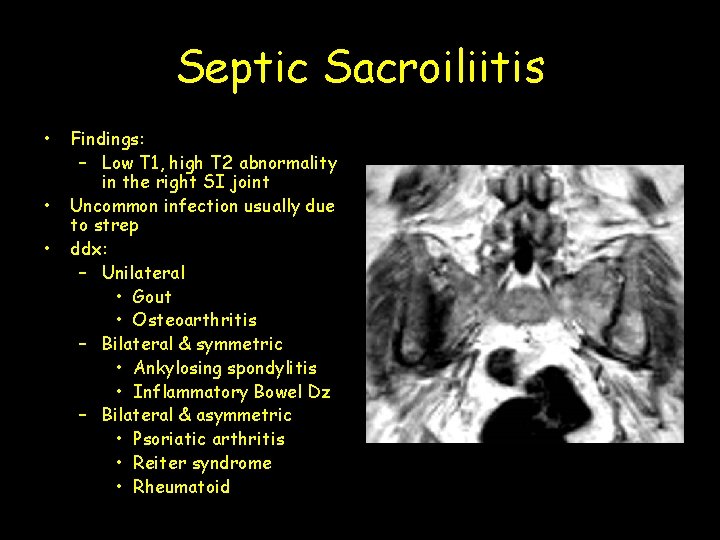

Septic Sacroiliitis • • • Findings: – Low T 1, high T 2 abnormality in the right SI joint Uncommon infection usually due to strep ddx: – Unilateral • Gout • Osteoarthritis – Bilateral & symmetric • Ankylosing spondylitis • Inflammatory Bowel Dz – Bilateral & asymmetric • Psoriatic arthritis • Reiter syndrome • Rheumatoid